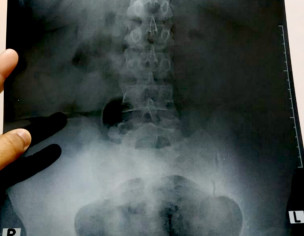

my mother is having sever pain in her lower back (the bone which joins to the hip ) she has been to doctors and have eaten the prescribed medicine but nothing seems to be working and eating these medicine make her dizzy as well . medicines she has been taking are Tonoflex Erwin 50 mg Miskoril 75 mg Pregy 75 mg methix please take a look at x ray and suggest something or really good doctor who could finally help her .please note that she is also a bp patient but her bp is normal these days .shukria

her xrays show spondylolisthesis with OA in hip and her vertebras. without treating spondylolisthesis, her pain will not go away since no medication can treat that. in Chicago USA we have been treating this successfully for over 22 years.

The quality of uploaded xrays is not clear though I do not see anything serious in these xrays.